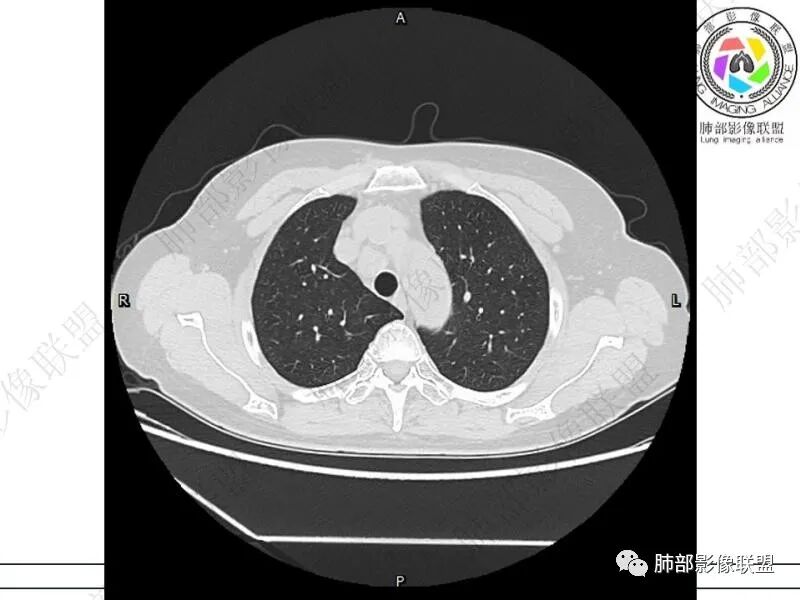

摘星空竹子:两肺胸膜下多发实性结节、磨玻璃影及实变影,短期复查病变有所进展,考虑感染性病变,隐球菌可能,患者有右半结肠癌手术史,转移不能除外。

简单:双肺及胸膜下多发小结节,双下肺胸膜下宽基底团块影,短期内病灶进展考虑炎性病变,隐球?患者ca术后,双肺小结节随诊除外转移

媛:肠癌术后,免疫力低下。两肺胸膜下结节及实变影,实变影长轴平行于胸膜,密度均匀,边界偏清,周围有晕征,短期复查进展,虽隐球菌荚膜抗原检测阴性,还是考虑隐球菌,鉴别OP

谢加平:结肠癌术后史,两肺胸膜下多发结节及斑块实变病灶,实边边界平直征(亚急性和慢性病变过程),双肺下叶后基底段胸膜下为甚,与胸膜平行特点,见支气管充气征,边缘模糊的GG0,首诊2022年11月18日肺部CT,与治疗11月28日对比,病灶未吸收,双肺下叶胸膜下病灶有侧向融合特点,综合分析符合炎性肉芽肿,隐球菌感染。

良孑:两肺胸膜下多发相类似结节,部分结节有晕及晕中软毛刺,部分结节侧向融合,长轴与胸膜平行,结节边缘可见刀切征,右半结肠癌术后免疫力低下,综合考虑支持隐球菌

2.影像特征:双肺胸膜下多发实性结节、磨玻璃影及实变影,胸膜下优势分布、晕征、胸膜下脂肪间隙存在,部分病灶边界平直征,有侧向融合趋势。